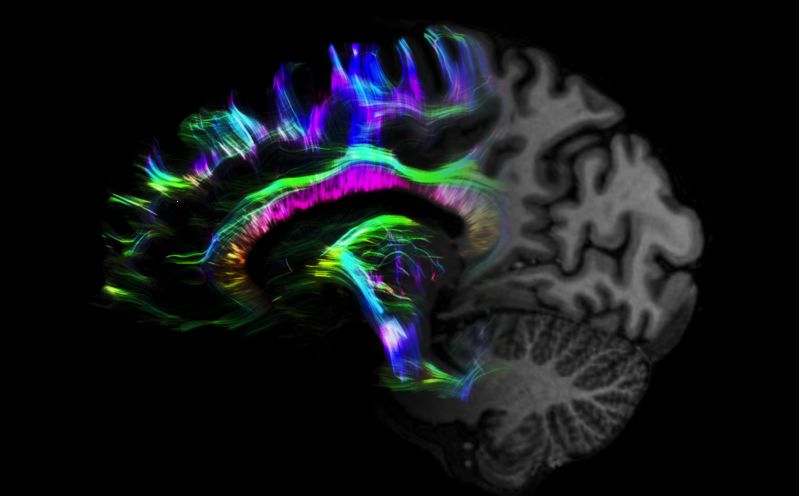

MAGNETOM Terra在業(yè)界首次實(shí)現(xiàn)了兩倍于傳統(tǒng)7T的超強(qiáng)梯度性能,實(shí)現(xiàn)超快速、超高效、超高分辨功能磁共振成像。如此高性能的梯度系統(tǒng)無論對于科研還是臨床都帶來了更多可能。

1毫米的各向同性分辨率DTI:神經(jīng)纖維束的交叉細(xì)節(jié)顯示

但近年來,西門子與科研機(jī)構(gòu)共同研究發(fā)現(xiàn),7T提供了數(shù)倍于傳統(tǒng)3T磁共振的信噪比和空間分辨率,在神經(jīng)、血管、腫瘤、骨關(guān)節(jié)等多個方面都會帶來全新的突破性進(jìn)展。尤其是在目前常規(guī)影像設(shè)備難以診斷的神經(jīng)退行性疾病如阿茲海默氏病、帕金森病等疾病的發(fā)病機(jī)理、早期診斷、治療方案確定以及治療效果評估上,有著極大的潛力。